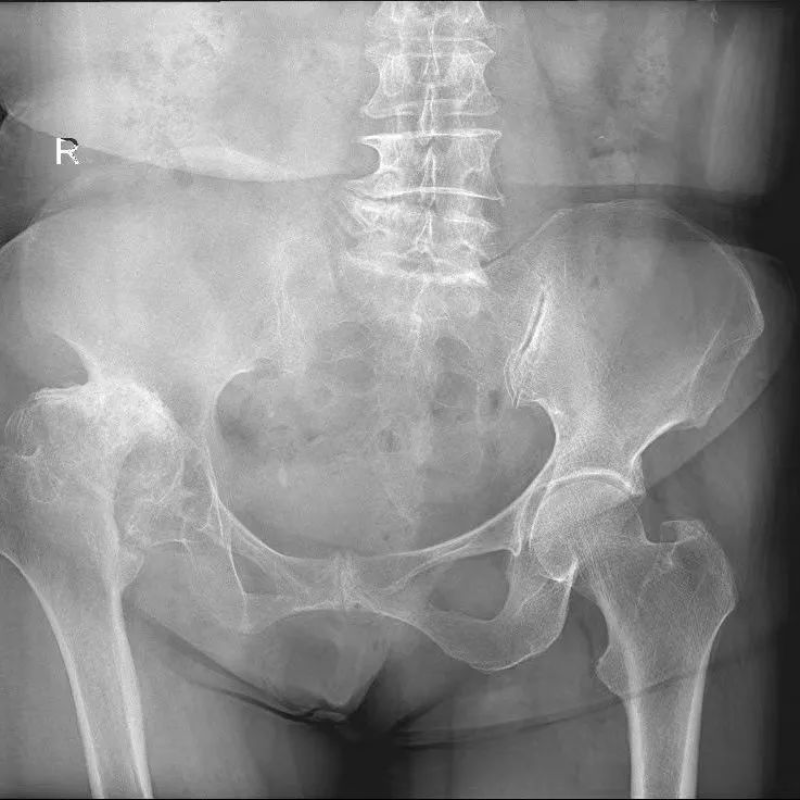

△術(shù)前

文章配圖

50多歲的朱大哥,20多年前因為車禍傷導(dǎo)致股骨頭缺血性壞死,一直一瘸一拐走路,就診時,右側(cè)髖關(guān)節(jié)股骨頭基本消失,髖臼磨損嚴(yán)重,關(guān)節(jié)已接近融合,肢體短縮有6-7cm,通過術(shù)前AI規(guī)劃,能精準(zhǔn)確定截骨的位置,髖臼杯安放的角度和尺寸等。手術(shù)進(jìn)展順利,術(shù)后關(guān)節(jié)功能恢復(fù)良好,肢體短縮明顯糾正無神經(jīng)損傷等并發(fā)癥,一個月后復(fù)查關(guān)節(jié)穩(wěn)定,患者從此告別一瘸一拐的日子。